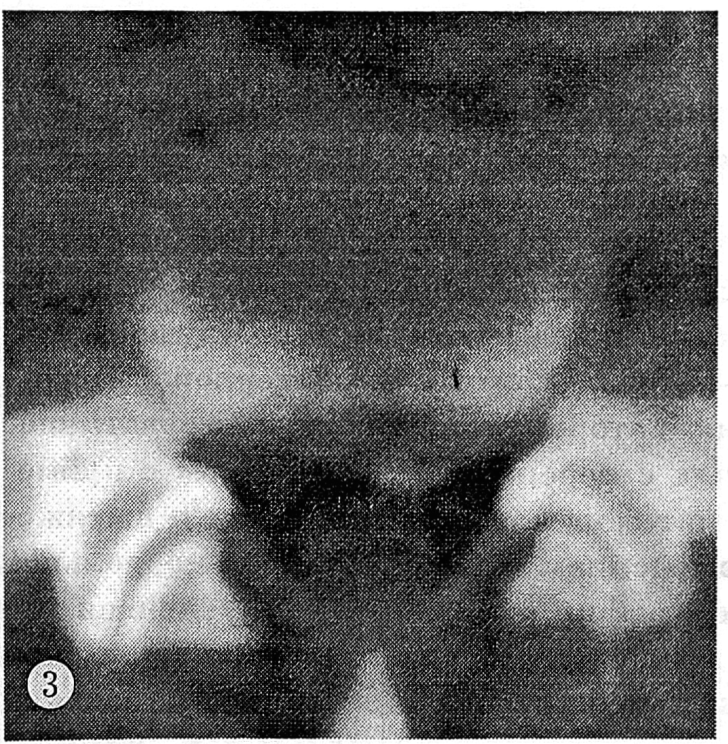

Выявлена статистически достоверная зависимость степени стеноза от продолжительности лечения при однотипном местном воздействии. У больных, получавших физиотерапию более года, а иногда и более 15 лет, на компьютерных томограммах поясничного отдела позвоночника обнаруживались признаки оссификации задней продольной связки, усугубляющей компрессионный синдром (рис. 3).

Рис. 3. Оссификация задней продольной связки (компьютерная томограмма).